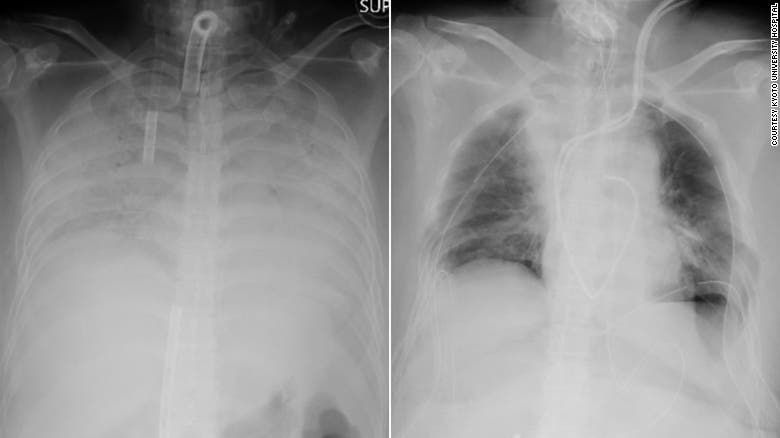

رئتا المريضة قبل وبعد العملية